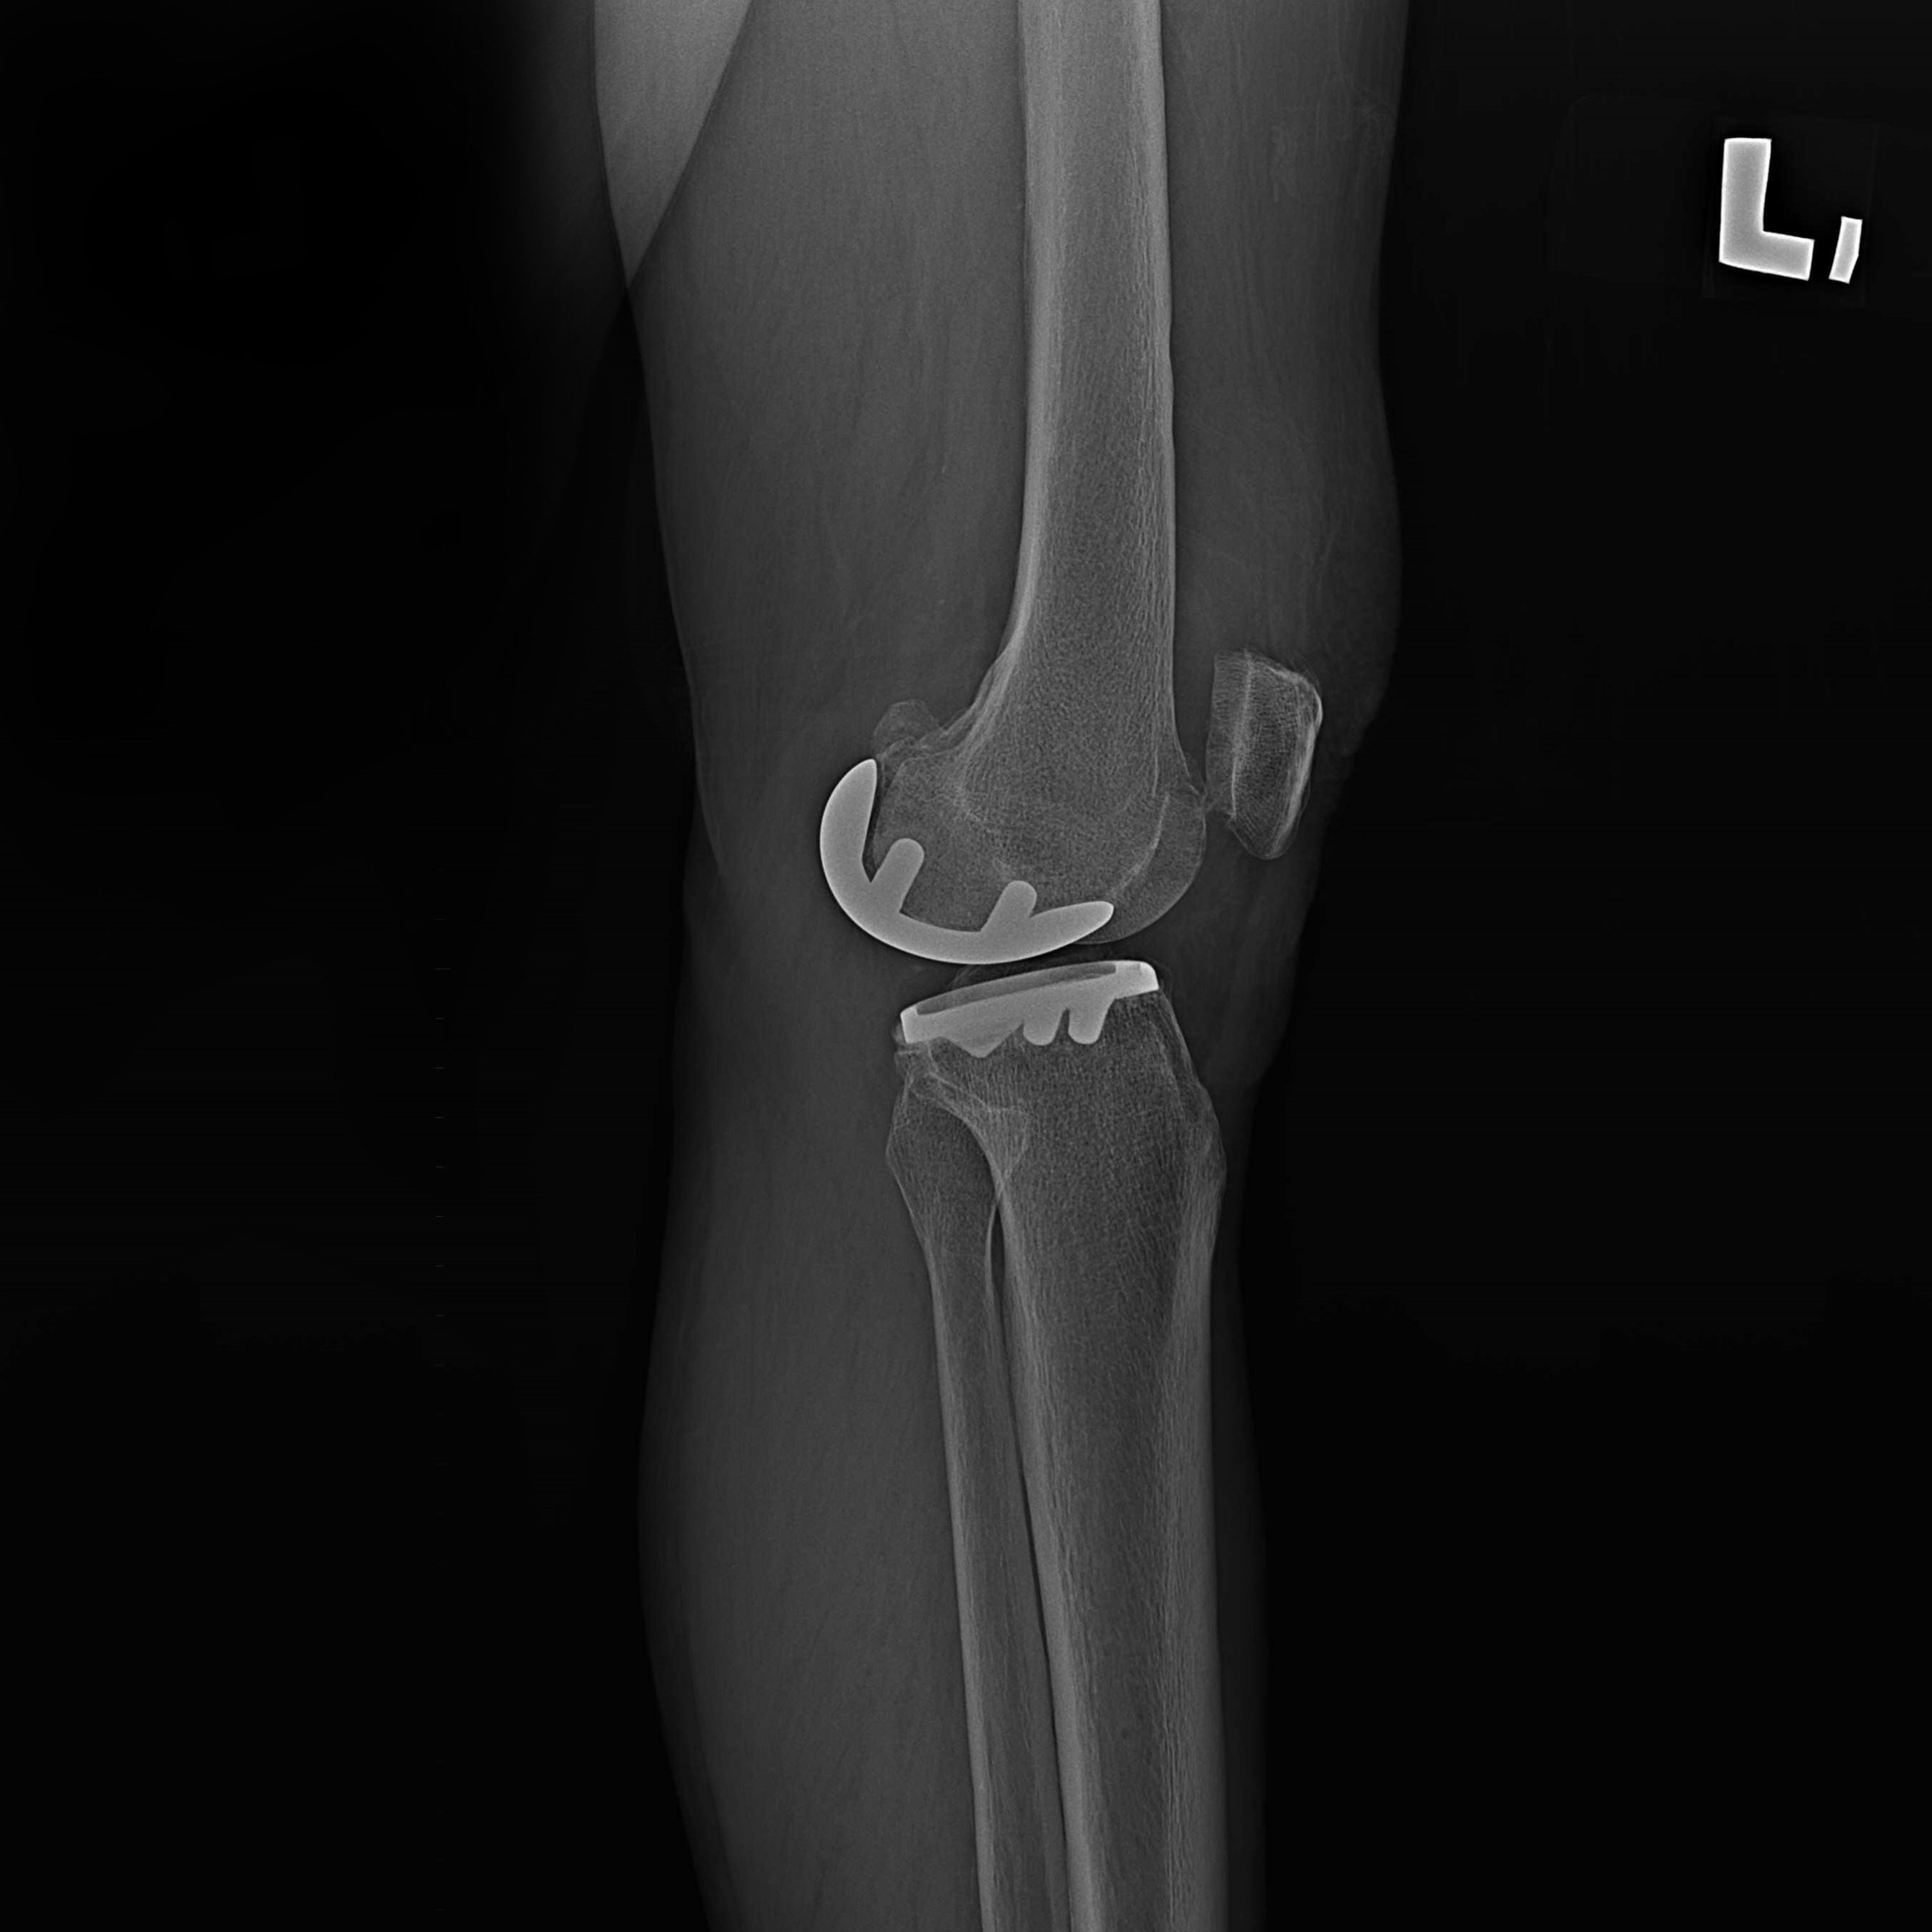

機器手臂手術 首頁 案例分享 膝關節手術 機器手臂手術 蔡女士 78歲 術前 術後 陳女士 70歲 術前 術後 術前 術後 ANGEVINE女士 73歲 術前 術後 U.S.A Mark 73歲 術前 術後 藍女士 78歲 術前 術後